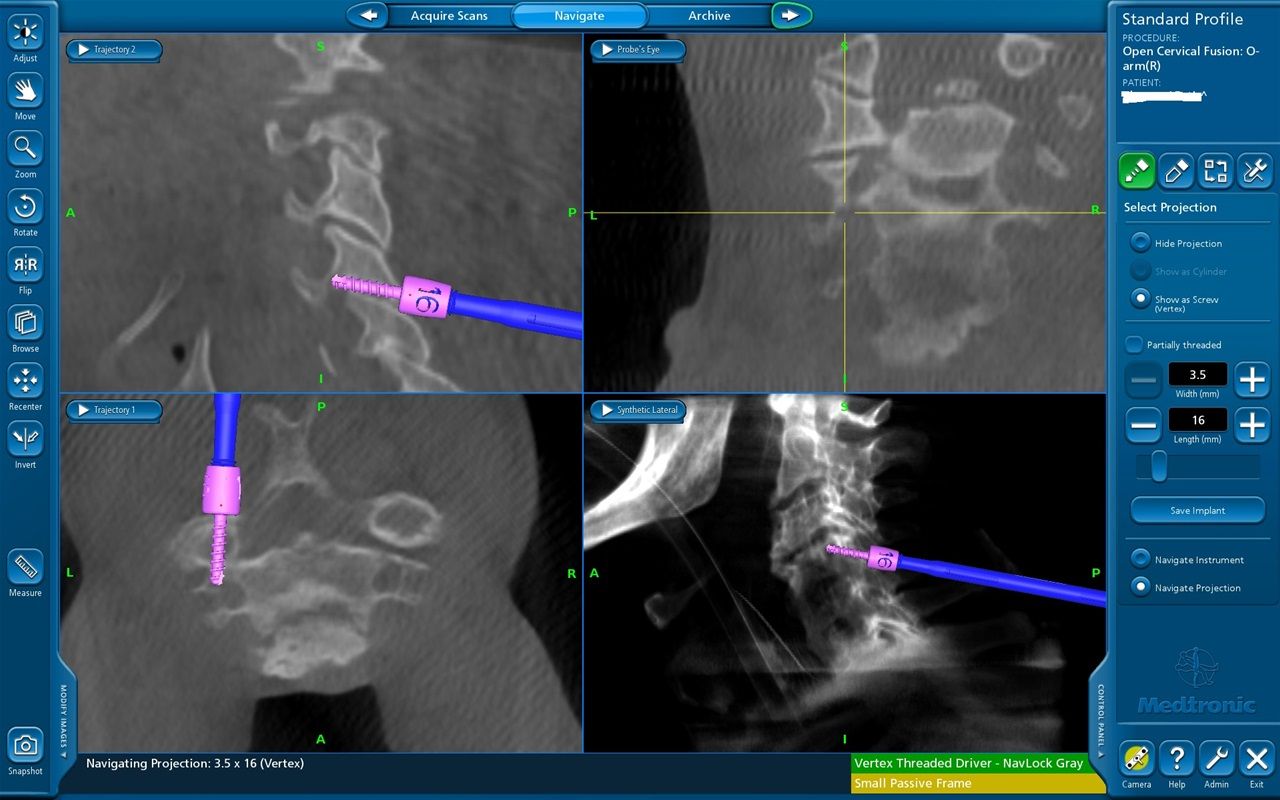

Νευροπλοήγηση με Stealth Station και διεγχειρητική απεικόνιση με 0 ARM.

Διεγχειρητική απεικόνιση οπίσθιας σπονδυλοδεσίας ΑΜΣΣ με O ARM